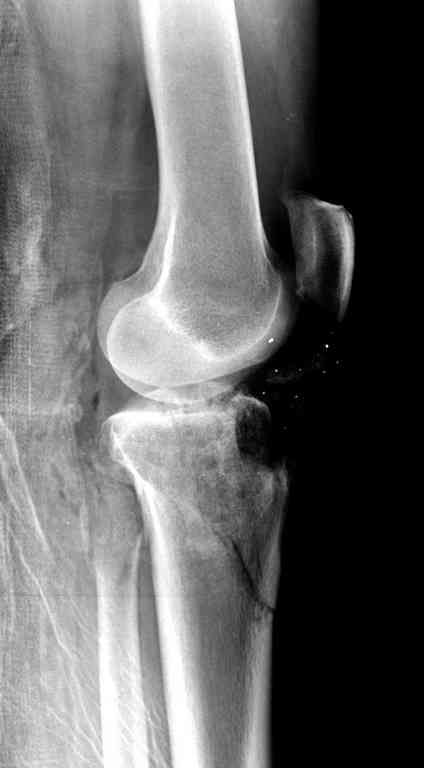

Пожалуйста, снимки.

Все ипсилатеральные переломы относятся к категории нестабильных, и лечение их бывает сложным из-за двойного перелома вокруг сустава (floating joint). Основная тактика состоит в проведении поэтапного лечения с окончательной фиксацией cуставной поверхности.

На первом этапе с задачей справляется наружный фиксатор, который создает благоприятные условия для закрытия ран и контролирует длину конечности. На данном этапе рекомендована КТ, чтобы увидеть топографию фрагментов для расчета направления фиксирующих элементов.

Состояние мягкотканого покрытия подскажет о готовности к окончательной фиксации. При дефектах кости придерживаются тактики максимального сохранения костной массы.

Здесь применение материала Plexur http://www.plexur.com для пластики при дефектах кости у больной с огнестрельной раной латерального тибиал плато с повреждением малоберцового нерва. Несмотря на интактный медиальный мышелок, для профилактики от вальгуса установлен АВФ и сделана ангиограмма.

После нескольких обработок и вакуумирования, поэтапно сделана фиксация тибиального бугра шурупами. И окончательную фиксацию закончили латеральной пластиной для тибиал плато и установкой пластического материала.